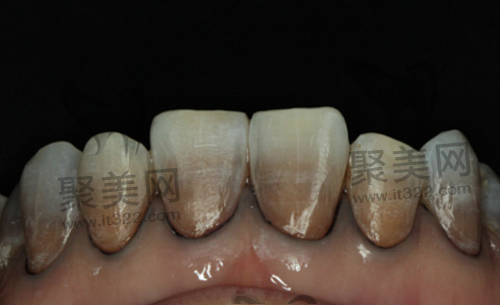

中期段四环素牙的牙齿颜色有棕黄色或者黑灰色不等

重度四环素牙牙齿表面有损伤,颜色为褐色或灰黑色,牙釉质发育不全